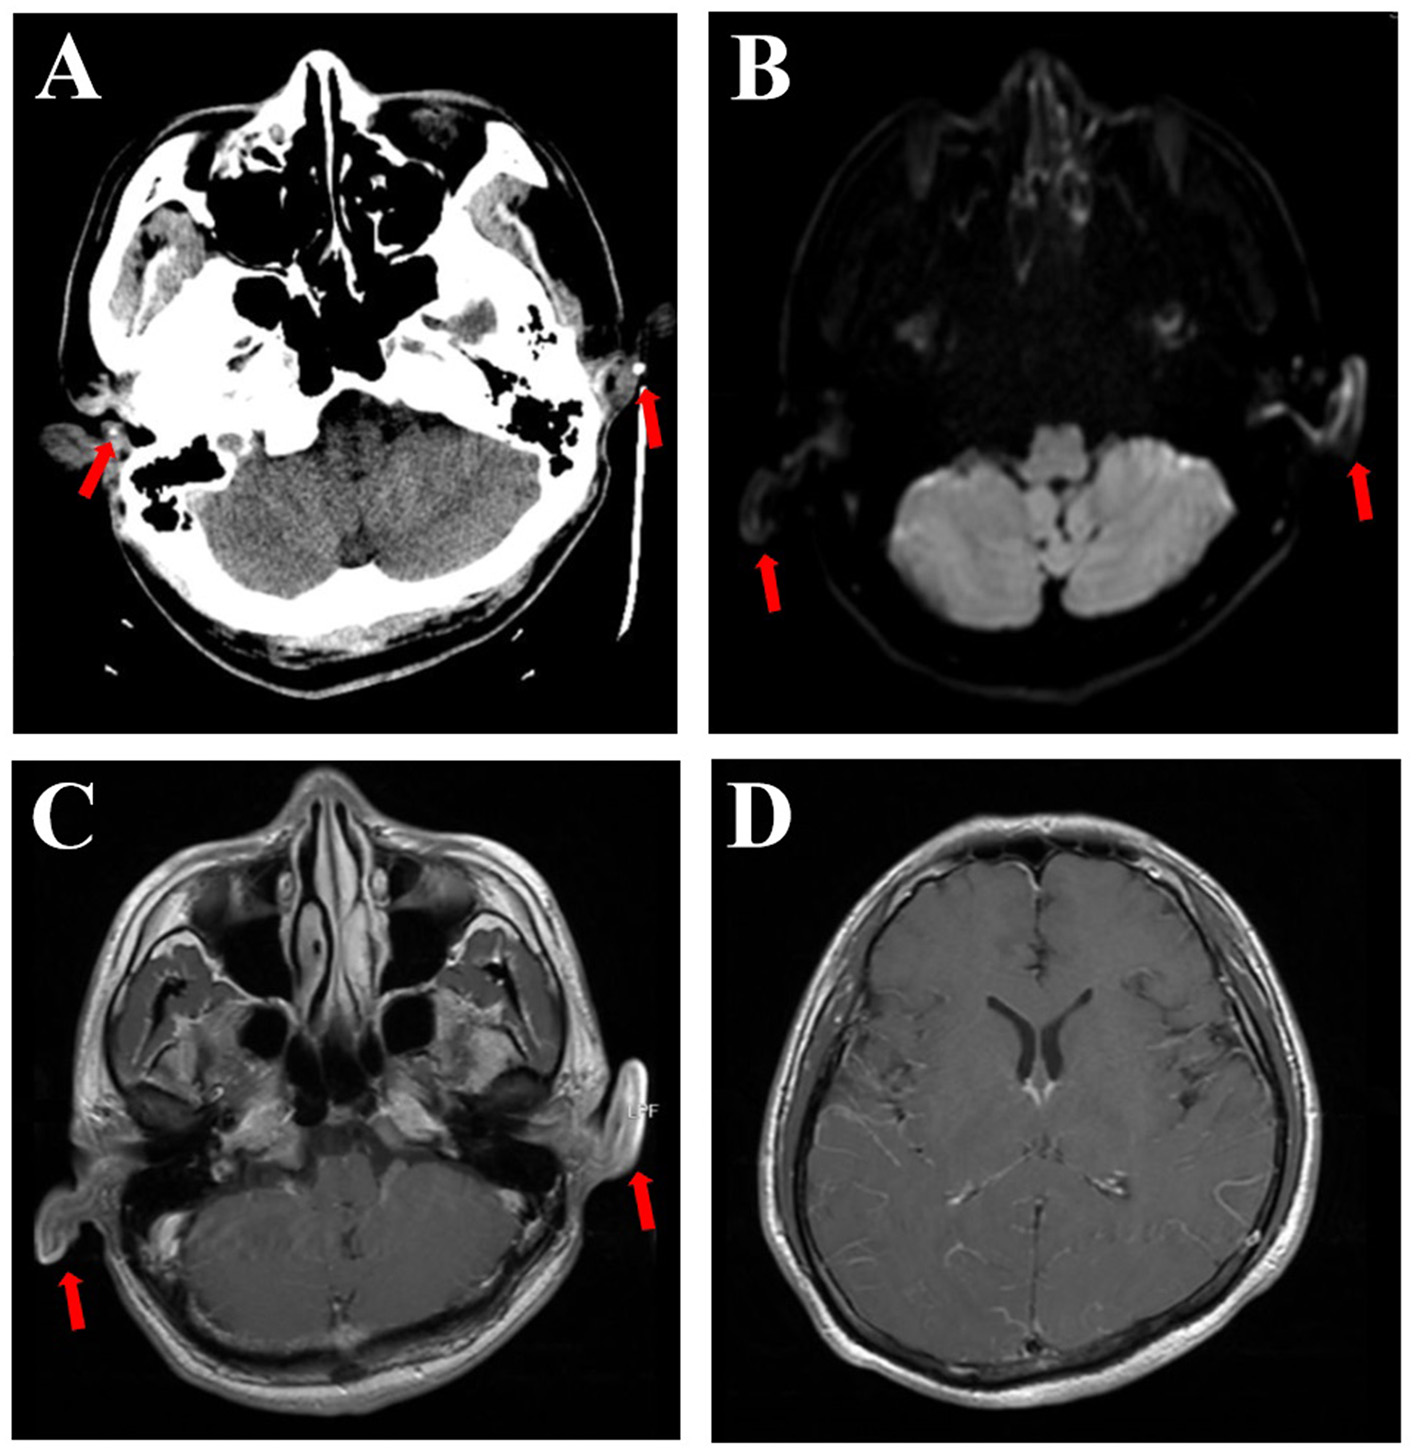

Upon admission, vital signs were as follows: body temperature 38.9°C, pulse 83 bpm, respiratory rate 19/min, and blood pressure 123/72 mmHg. The patient was somnolent but arousable and responded slowly. The cranial nerve examination was normal, except for red eyes. Motor system examinations revealed left arm paresis graded 4+ on the Medical Research Council (MRC) scale. Kernig's signs were positive, with no neck resistance. There were no abnormalities in the reflex, sensory, or coordination systems. Laboratory tests showed a white blood cell count of 14,300/μL (neutrophils 88.6%), C-reactive protein of 17.6 mg/L, erythrocyte sedimentation rate of 60 mm/h, and procalcitonin within the normal range. Aspirin and clopidogrel were discontinued upon admission to the hospital ward. Ceftriaxone and acyclovir were continued. Lumbar puncture was performed the day after admission, with an opening pressure of 175 mmH2O. CSF analysis showed 2 leukocytes/μL, 736.5 mg/L of protein, and 50.0 mg/dL of glucose (103 mg/dL of simultaneous blood glucose). CSF adenosine deaminase, occult blood, Gram stain, acid-fast staining, ink staining, tuberculosis, and herpes virus antibodies were all negative. CSF cytology revealed a mixed-cell inflammatory response. CSF metagenomic next-generation sequencing revealed the presence of streptococcus. Contrast-enhanced brain MRI demonstrated an increased enhancement of the pia mater (Figure 3), with no abnormal signals in the brain parenchyma. Abnormal DWI signals were observed in the bilateral auricles (Figure 3). EEG revealed a moderate slow-wave change, which was more pronounced on the right side. Both peripheral blood and CSF autoimmune encephalitis antibody spectrum tests, including anti-N-methyl-D-aspartate receptor (anti-NMDAR), anti-leucine-rich glioma-inactivated 1 (anti-LGI1), anti-contactin-associated protein-like 2 (CASPR2), anti-gamma aminobutyric acid-B receptor (GABABR), anti-α-amino-3-hydroxy-5-methyl-4-isoxazolepropionic acid receptor 1 (anti-AMPAR1), anti-AMPR2, anti-immunoglobulin-like cell adhesion molecule 5 (anti-IgLON5), anti-dipeptidyl-peptidase-like protein 6 (anti-DPPX), anti-glutamic acid decarboxylase 65 (anti-GAD65), anti-metabotropic glutamate receptor 5 (anti-mGluR5), anti-glycine receptor (GlyR), and anti-R2R, were all negative. The T-SPOT.TB test and IgG4 were also negative.

Figure 3

Brain CT scan showing calcification (arrows), which can be seen in the polychondritic ears (A). DWI shows abnormal signals in the bilateral auricles (B, arrows). T1-weighted MRI with contrast showed abnormal signals and thickening of both ears (C, arrows) and increased enhancement of the pia mater (D).

Brain MRI findings in patients with RP-associated meningoencephalitis include non-specific white matter changes and preferential involvement of the medial temporal lobes (9). Nine patients have been reported with meningeal enhancement on contrast-enhanced T1-weighted MRI, including those from our center. However, because some cases did not state whether brain MRI was performed with or without contrast, the prevalence of meningeal enhancement was unclear. Calcification and thickening in the ears on CT scans (2, 9) and abnormal DWI and T1-weighted signals in the auricles on MRI scans (9) could also clarify the diagnosis but may easily be neglected.